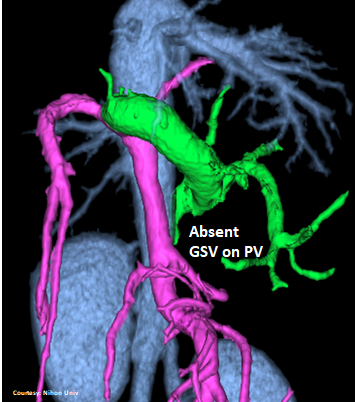

PRE-HEPATIC ENTRANCE

(Absent GSV)

Does the GASTROSPLENIC VEIN (GSV) enter the CAUDAL VENA CAVA (CdVC) directly?

WEISSE 2022

slide19

“LGC +PancV -GSV” Left Gastro-Caval Shunt with Pancreatic Vein contribution and absent Gastro-splenic vein (GSV does not enter PV)

Courtesy: Nihon Univ